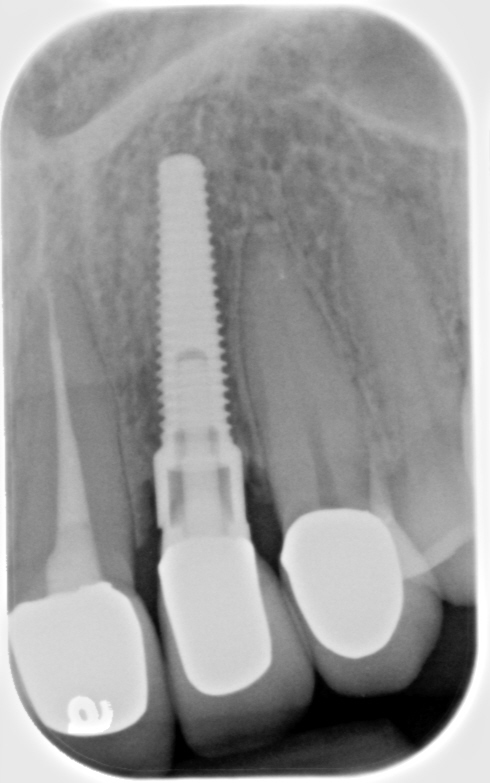

Screw loosening and fracture (Figure 3 and Figure 4) have been consistent problems in implant dentistry.6 Several adaptations have been made to the screw and implant design to minimize these issues, such as the transition from an external to internal connection and changing both the screw composition and coating. Implant manufacturers offer various implant connection and screw designs, and these designs are modified as newer and enhanced materials become available.

Fig 3. Fractured abutment screw.

Figure 3

Fig 4. Bending of the abutment prongs as a result of motion caused by screw fracture.

Figure 4